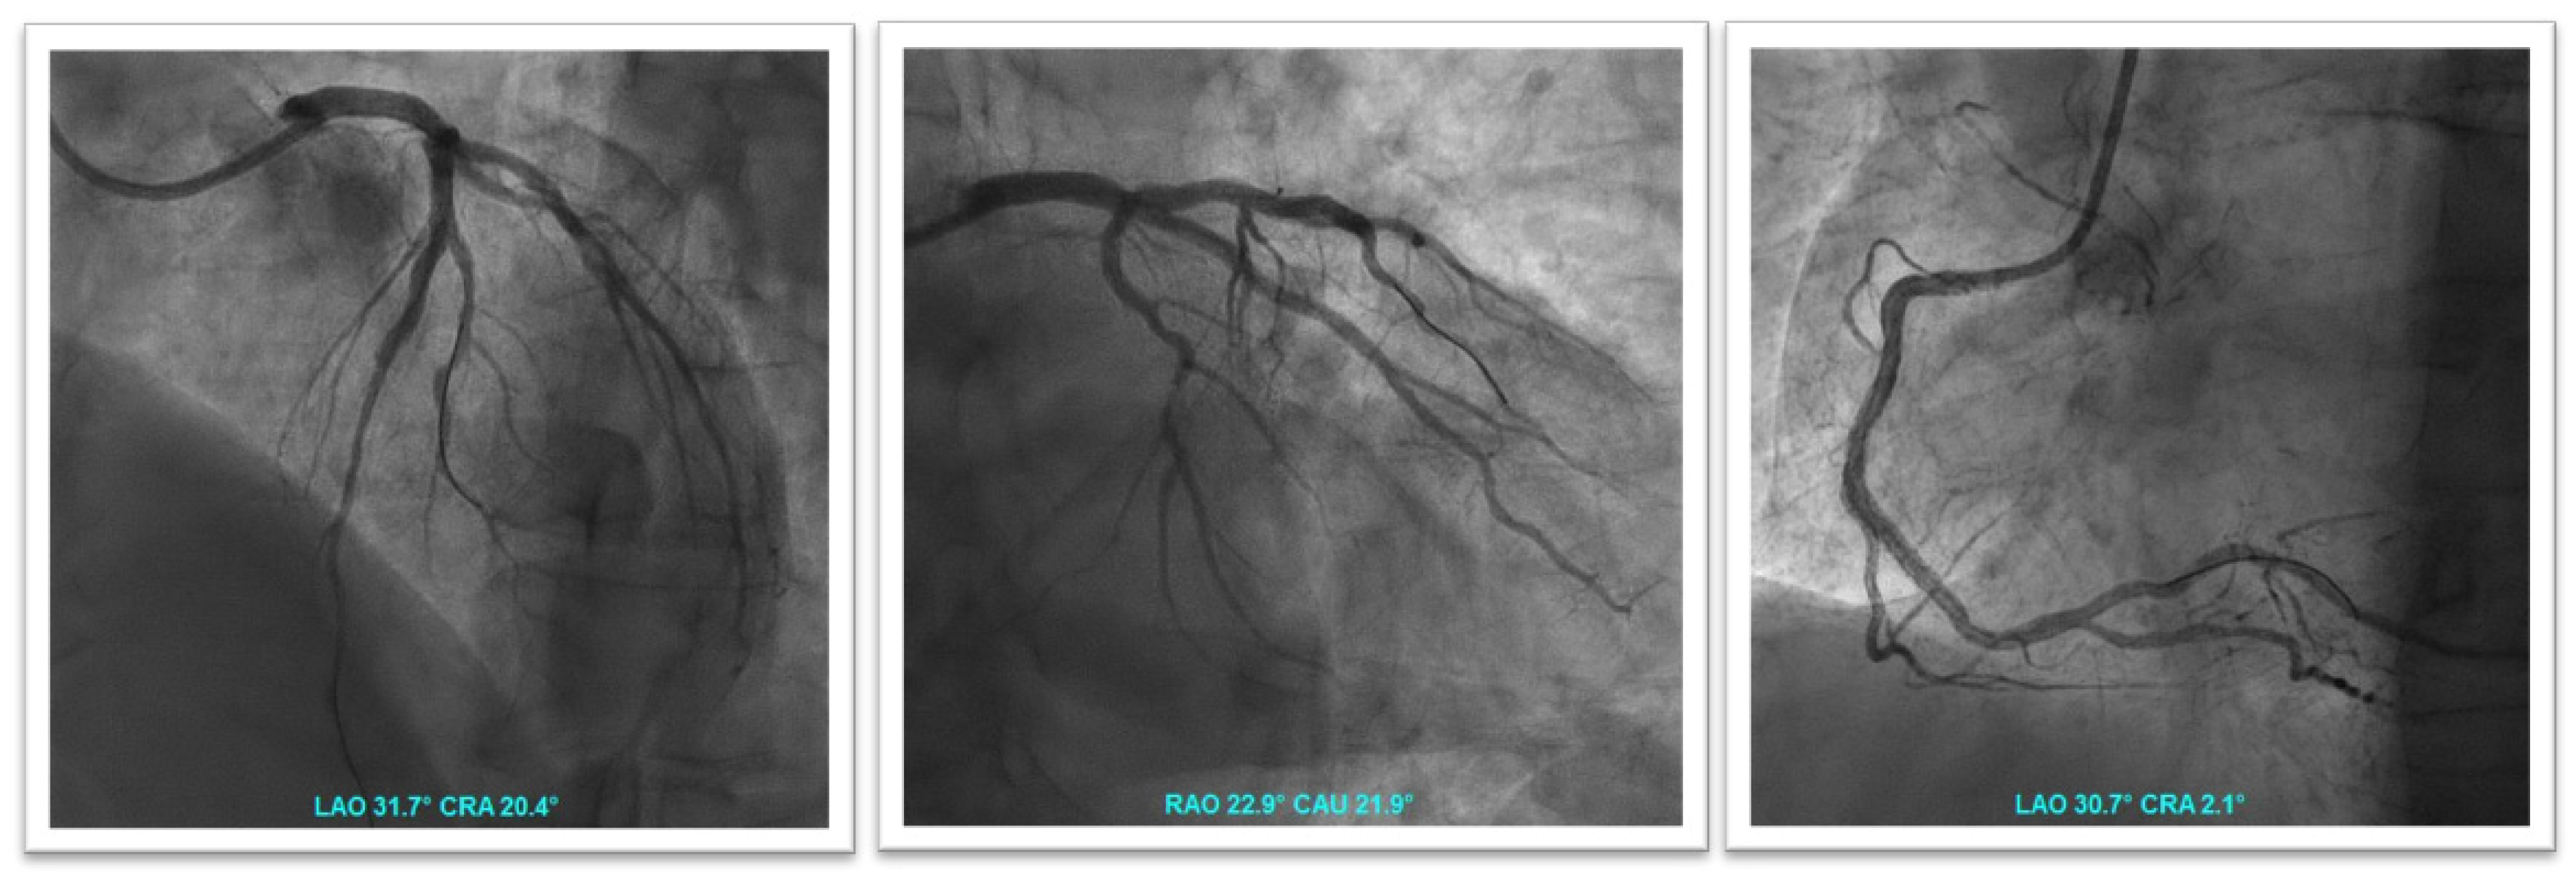

We report five cases of patients with AF presenting with ACS and/or treated by PCI to show the decision-making work-up in clinical practice regarding the choice of antithrombotic regimen. In this scenario, DOAC should be preferred over VKA because of their favorable risk/benefit profile, as recommended by the current guidelines. The choice of the optimal antithrombotic therapy (TAT or DAT) and the duration of TAT (one week or one month) depends on a careful evaluation of the individual patient’s hemorrhagic and ischemic risk factors, as well as evaluation of the coronary anatomy profile and procedural complexity in order to identify patients who might benefit from prolonged TAT and those who might have an excessive risk of bleeding. The choice of specific DOAC and dosage represent the most important challenge in these patients, and should be based on clinical characteristics and hemorrhagic and ischemic risk (previous OAC therapy, frailty, renal function, presence of criteria for dose reduction, etc.). The different factors to consider when determining the optimal antithrombotic regimen for individual patients are summarized in Figure 6. Moreover, in Figure 7, we suggest a practical algorithm for the choice of antithrombotic treatment in patients with atrial fibrillation presenting with acute coronary syndrome and/or undergoing PCI.

Figure 6.

Factors for physicians to consider when determining the optimal antithrombotic regimen for individual patients with atrial fibrillation and acute coronary syndrome or PCI.

Figure 7.

Proposed algorithm for the choice of antithrombotic strategy in patients with atrial fibrillation presenting with acute coronary syndrome and/or undergoing PCI. * evaluate continuation until hospital discharge. DOAC: direct oral anticoagulant; OAC: oral anticoagulant; TAT: triple antithrombotic therapy; DAT: dual antithrombotic therapy.